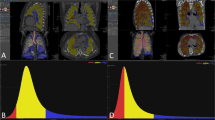

Graphs show receiver operating characteristics (ROC) analyses for the best classifying models of GAP1 versus GAP2 stage. ROC analysis indicates accuracy, sensitivity, and specificity of the best performing models applied on the (a) independent testing dataset and on the (b) original (non-augmented) dataset. Panel c showing ROC analyses for classifying GAP stage with visual analysis of extent of fibrosis (fibrosis > 20%) and coarseness of fibrosis